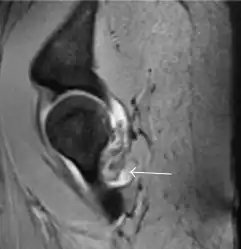

In adults, MRI is currently playing a definite role in the assessment of osteoarthritis. Although traditionally belonging to the arena of radiographs, the role of MRI has been stressed after the term femoral acetabular impingement was coined in 2003. Growing interest has been focused in accurate diagnosis of the acetabular and femoral morphological abnormalities that may lead to early osteoarthritis.[1]

MR imaging is considered paramount to these objectives, mainly when surgery is considered, due to the ability of MRI to portray the whole section of the femoral neck surface, as well as to image the labrum and articular cartilage.[1]

Diagnosis of impingement can only be achieved if, besides imaging findings, there are also clinical symptoms and positive impingement maneuvers.[1]

Most of the angles and measurements described in the plain radiograph section can be accurately reproduced on MRI. In addition, the superiority of MRI resolution with intra-articular contrast allows detection of labral and chondral abnormalities that may influence the choice of medical, percutaneous, or surgical management (Figure 9).[1]

Figure 9:

-

Sagittal T1 weighted image showing anterosuperior labral tear.[1] -

Sagittal T1 weighted image showing chondral lesion.[1] -

Sagittal CT-arthrography showing posteroinferior chondral injury.[1] -

Coronal CT-arthrography (d) showing ligamentum teres tear.[1]

MR arthrography has proven superior in accuracy when compared to native MR imaging. It is considered the best technique to assess the labrum. Knowledge of the normal variable morphology of the labrum helps to differentiate tears from normal variants. A triangular shape is most commonly seen in 66% of asymptomatic volunteers, but round, flattened, and absent labra can also be found in asymptomatic populations. MR arthrography has demonstrated sensitivity over 90% and specificity close to 100% in detecting labral tears. Loose bodies are demonstrated as filling defects surrounded by the hyperintense gadolinium.[1]

Association between labral tears and chondral damage has been demonstrated. This underscores the interaction between cartilage and labrum damage in the progression of osteoarthritis. Chondral damage to the posteroinferior part of the acetabulum as a contrecoup lesion occurs in approximately one-third of pincer cases secondary to persistent abutment on the anterior part of the joint leading to a slight posteroinferior subluxation. This is considered a bad prognosis sign.[1]

MR arthrography can also demonstrate ligamentum teres rupture or capsular laxity, which are debated causes of microinstability of the hip. Elongation of the capsule or injury to the iliofemoral ligament or labrum may be secondary to microtrauma in athletes. MR can demonstrate abnormalities in these cases, such as increased joint volume or a ligamentum teres tear (Figure 9).[1]